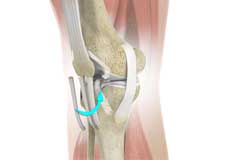

PCL Reconstruction

PCL reconstruction surgery is a procedure to correct torn posterior cruciate ligament (PCL) in the knee using a tissue graft taken from another part of the body, or from a donor.

PCL Injuries

Posterior cruciate ligament (PCL), one of the four major ligaments of the knee, is situated at the back of the knee. It connects the thighbone (femur) to the shinbone (tibia). The PCL limits the backward motion of the shinbone.